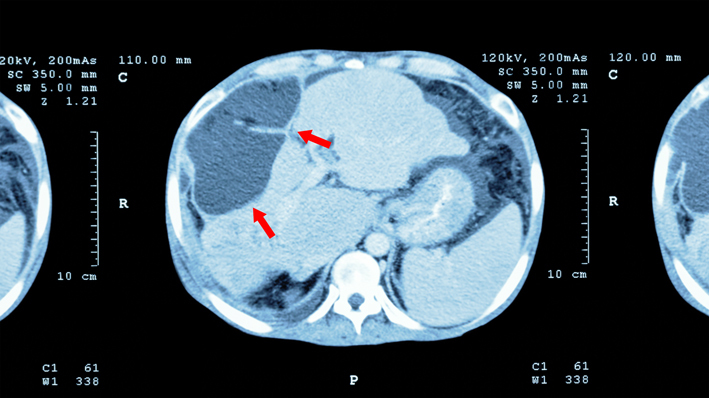

3. инструментальные методы диагностики, такие как ультразвук, компьютерная томография (КТ) или магнитно-резонансная томография (МРТ) с контрастом или без, которые позволяют врачу визуализировать орган и обнаружить новообразование.